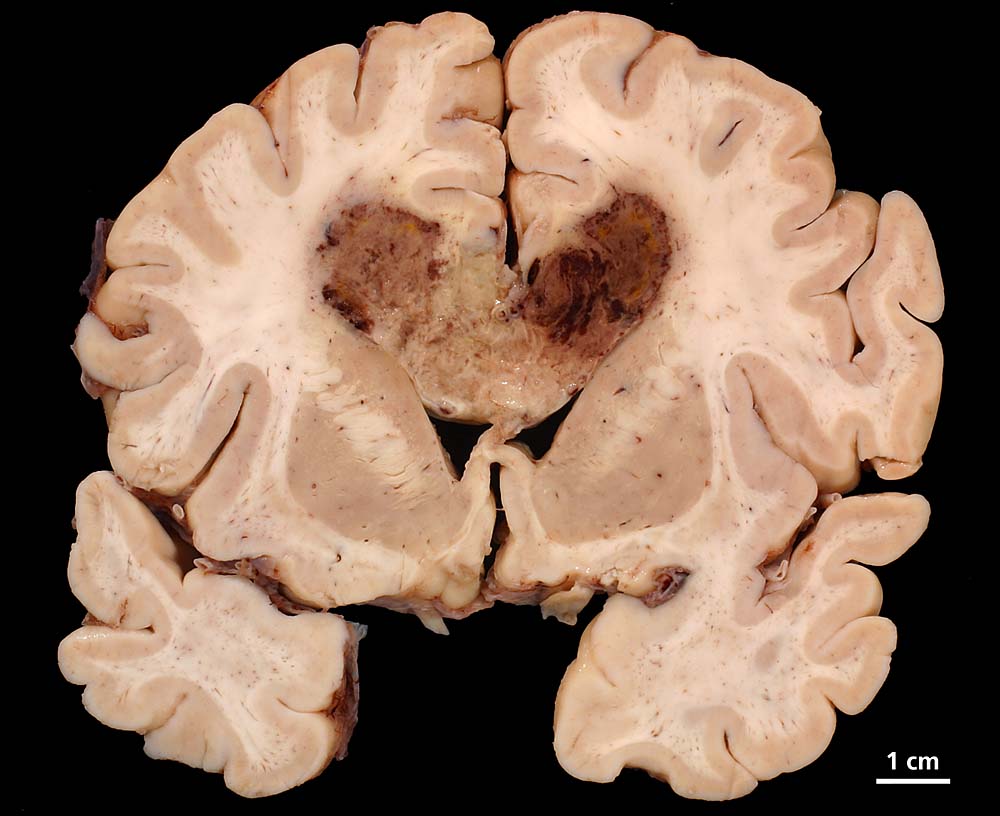

Morphologie:

Die Schnittfläche ist auffallend bunt. Dies ist bedingt durch ein Nebeneinander von graurotem vitalem Tumorgewebe, gelben Nekrosen, roten Einblutungen und gelegentlich grünlichen Gallertzysten.

Makroskopie